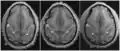

Position of marginal sulcus (shown in red). -

Transverse sections of brains of vervet monkey. It showing difference of the relative position of the left and right ascending ramus of the cingulate sulcus.